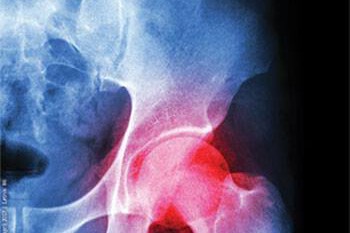

Zdravniška strokovna napaka

Odškodninska odgovornost proizvajalca medicinskih pripomočkov z napako